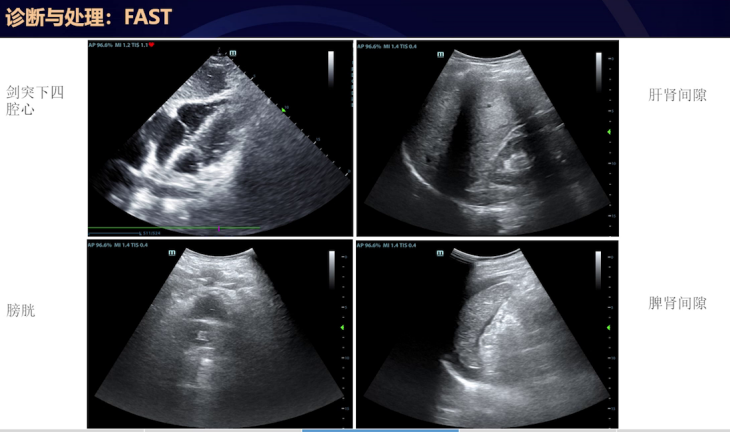

床旁FAST超声检查发现:剑突下四腔心图像显示心包腔内无明显积液,心脏收缩功能良好但容量欠;右上腹图像显示肝肾间隙、膈下无明显游离性液体;耻骨联合上图像显示膀胱周围无明显液性暗区;而左上腹图像显示脾脏周围有明显游离性积液。鉴于手术为下腹部手术,脾脏位置较高,与外科医生沟通后,持续监测脾脏周围游离性液体,发现其不断增加,高度怀疑为进行性出血。遂邀请外科和超声科医生,对脾脏周围游离性液体进行穿刺,抽出不凝血,证实为进行性出血。结合患者血流动力学不稳定,决定进行二次手术。

FAST是一种用于评估低血压和危重患者的超声检查,虽常用于创伤患者,但对任何危重患者都能提供关键信息。主要评估身体区域包括心包间隙、膈下间隙、肝肾间隙、脾肾间隙、结肠旁沟、盆腔(男性为膀胱直肠陷凹,女性为膀胱子宫陷凹即道格拉斯窝),以判断是否存在游离性液体,提示腹腔、腹膜后、胸腔内积血或心包积血,并评估心脏功能。

FAST超声探查体位主要为平卧位,适合围手术期患者。探查位置有右上腹、剑突下、左上腹、耻骨联合上。右上腹探头置于第8到第11肋间腋中线及腋后线,与肋骨平行,与身体长轴逆时针夹角45度,可观察右侧胸腔、膈下、肝肾隐窝等有无积液,还可观察膈肌判断胸腔与腹腔积液,以及判断膈神经阻滞情况。左上腹探头在左侧腋后线第6到9肋间,可让患者右侧卧位更好评估左侧相关区域。剑突下探头探查心包腔,评估心包积液及心脏功能,大量心包积液伴右室游离壁塌陷、心脏钟摆样运动等可能提示心包填塞。耻骨联合上探头可长轴或短轴扫查盆腔,寻找膀胱直肠陷凹或膀胱子宫陷凹的游离性液体。